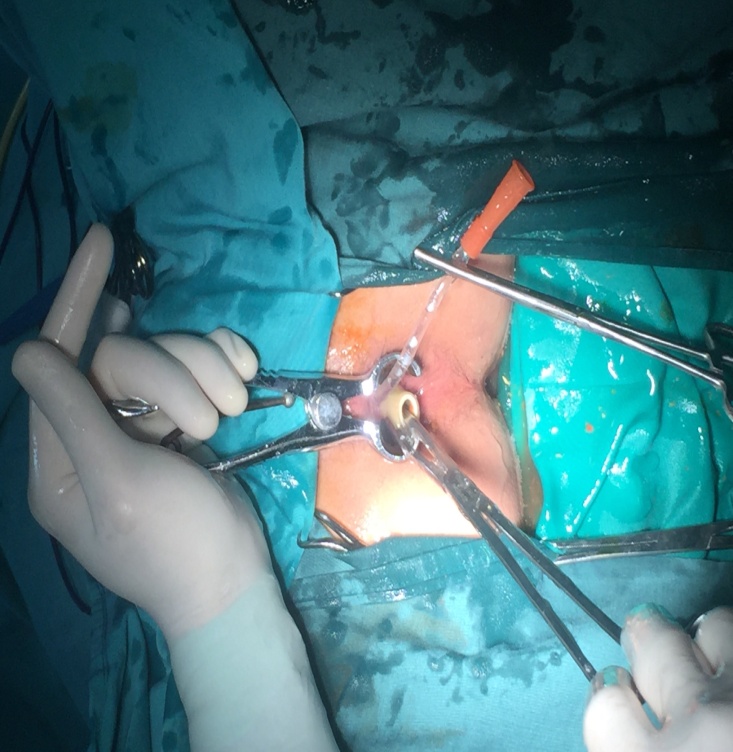

Kíp phẫu thuật đã mở bụng, mở đại tràng sigma lấy được cả đoạn vòi nước và đầu xả dài khoảng 45 cm. Dị vật gây tổn thương và gây viên niêm mạc ruột nên các bác sỹ đã đưa đại tràng sigma ra ngoài làm hậu môn nhân tạo và dự kiến sẽ lập lại lưu thông ruột (nối lại ruột) khi đủ điều kiện. Hiện tại sức khỏe bệnh nhân đã được hồi phục và dự kiến ra viện sau phẫu thuật 7 đến 10 ngày.

Mở đại tràng sigma lấy dị vật |